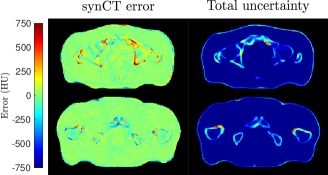

We tested the ability of the proposed network to better predict associated uncertainties in the synCT error. To verify that we produce clinically viable samples for treatment planning, we quantified the distribution of regression z-scores for the multi-task heteroscedastic and homoscedastic models. In the former, the total predictive uncertainty is the sum of the intrinsic and parameter uncertainties. This leads to a better approximation of the variance in the model. In contrast, the total uncertainty in the latter reduces to the variance of the stochastic test-time samples. This is likely to lead to a miscalibrated variance. A goodness of fit test was performed, showing that the homoscedastic z-score distribution is not normally distributed (, ) in contrast to the heteroscedastic model (, ). This is apparent in Fig.3 where there is greater confidence in the synCT produced by our model in contrast the homoscedastic case.

The predictive uncertainty can be exploited for quality assurance (Fig. 4). There may be issues whereupon time differences have caused variations in bladder and rectum filling across MR and CT scans causing patient variability in the training data. This is exemplified by large errors in the synCT at the rectum (Fig. 4) and quantified by large localised z-scores (Fig. 4g), which correlate strongly with the intrinsic and parameter uncertainty across tasks (Fig. 2 and 4).